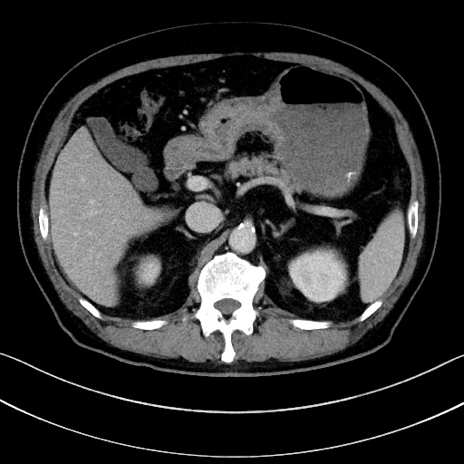

症例15(横断像)

【症例】70歳代男性

【主訴】腹痛

【現病歴】今朝から腹痛あり。全体的に痛い。特に左上の方。排ガスが今日はない。冷や汗が出る。

【既往歴】直腸癌術後

【身体所見】左側腹部〜上腹部に圧痛あり。腹膜刺激症状明らかなではない。軽度反跳痛。左下腹部に術後瘢痕あり。

【データ】WBC 7700、CRP 0.02